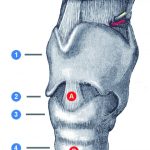

Hier konnte im MRT eine Patelladysplasie und röntgenologisch die klinisch diagnostizierte Patellalateralisation bestätigt werden. Als Nebenbefund zeigte sich in der MRT eine zystisch tumoröse Raumforderung von etwa 2 x 1 x 2 cm im Bereich des distalen Femurs mit der Verdachtsdiagnose: „Gutartiger Knochentumor im Sinne eines Enchondroms“. Die Diagnose wurde durch Röntgenbild, MRT und CT, aber auch sonographisch gesichert.

Bevorzugte Lokalisationsorte der stammfernen solitären Enchondrome sind mit etwa 48 % das Hand- und 6 % das Fußskelett. Die Manifestation „stammnah“ und damit außerhalb der Hand- und Fußskelette ist dagegen eher selten; sie betreffen nur um 40 % aller solitären Enchondrome, wobei hier die Femurregionen mit etwa 10 % einzeln aufgeführt werden [8].

Die diagnostischen Möglichkeiten zur Klärung des Befundes und prognostischen Aussagen sind vielfältig. Zeigt sich im Röntgenbild und CT der stammnahen Enchondrome eine mehr oder weniger zentrale, metaphysär gelegene zystische Struktur mit einzelnen Aussparungen, sind sie in der Regel scharf konturiert mit deutlichem Sklerosesaum [2, 4, 8]. Fleckförmige Verkalkungen können auftreten. Zusätzlich sind mittels MRT, Angiographie und Szintigraphie die wichtigsten Differentialdiagnosen des Knocheninfarktes und Chondrosarkoms sowie die Dignitätstendenz abgrenzbar [4, 9]. In unserem Fall konnte durch Röntgenbild, MRT und CT, aber auch sonographisch der Befund eindeutig identifiziert und differenziert werden. Gerade die CT-Untersuchung lieferte in unserem Fall keine Hinweise für große Tumoraussparungen mit prognostischer Relevanz für geringes Frakturrisiko.